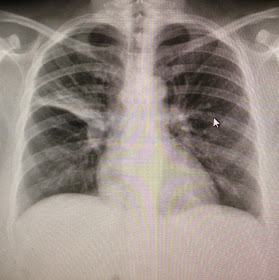

Notice the nice clear lung fields. Notice how there is no vicious, nasty plague abiding in there. Now, compare that to this:

That is my wife's actual chest X-ray last week when she was first admitted. Almost the entire right upper lung (that's on the left of the picture, by the way) is involved with some kind of evil nastiness. What you can't see (that the CT scan showed) is that in addition to a very dense consolidation of her entire right upper lobe, she had areas of pneumonia in the left upper lobe, lower lobe, and lingula as well. That explains why she was having fevers, chills, and a nearly-constant cough. And THAT is what she was living with while still going to work, making dinner, doing laundry, and taking care of her family.